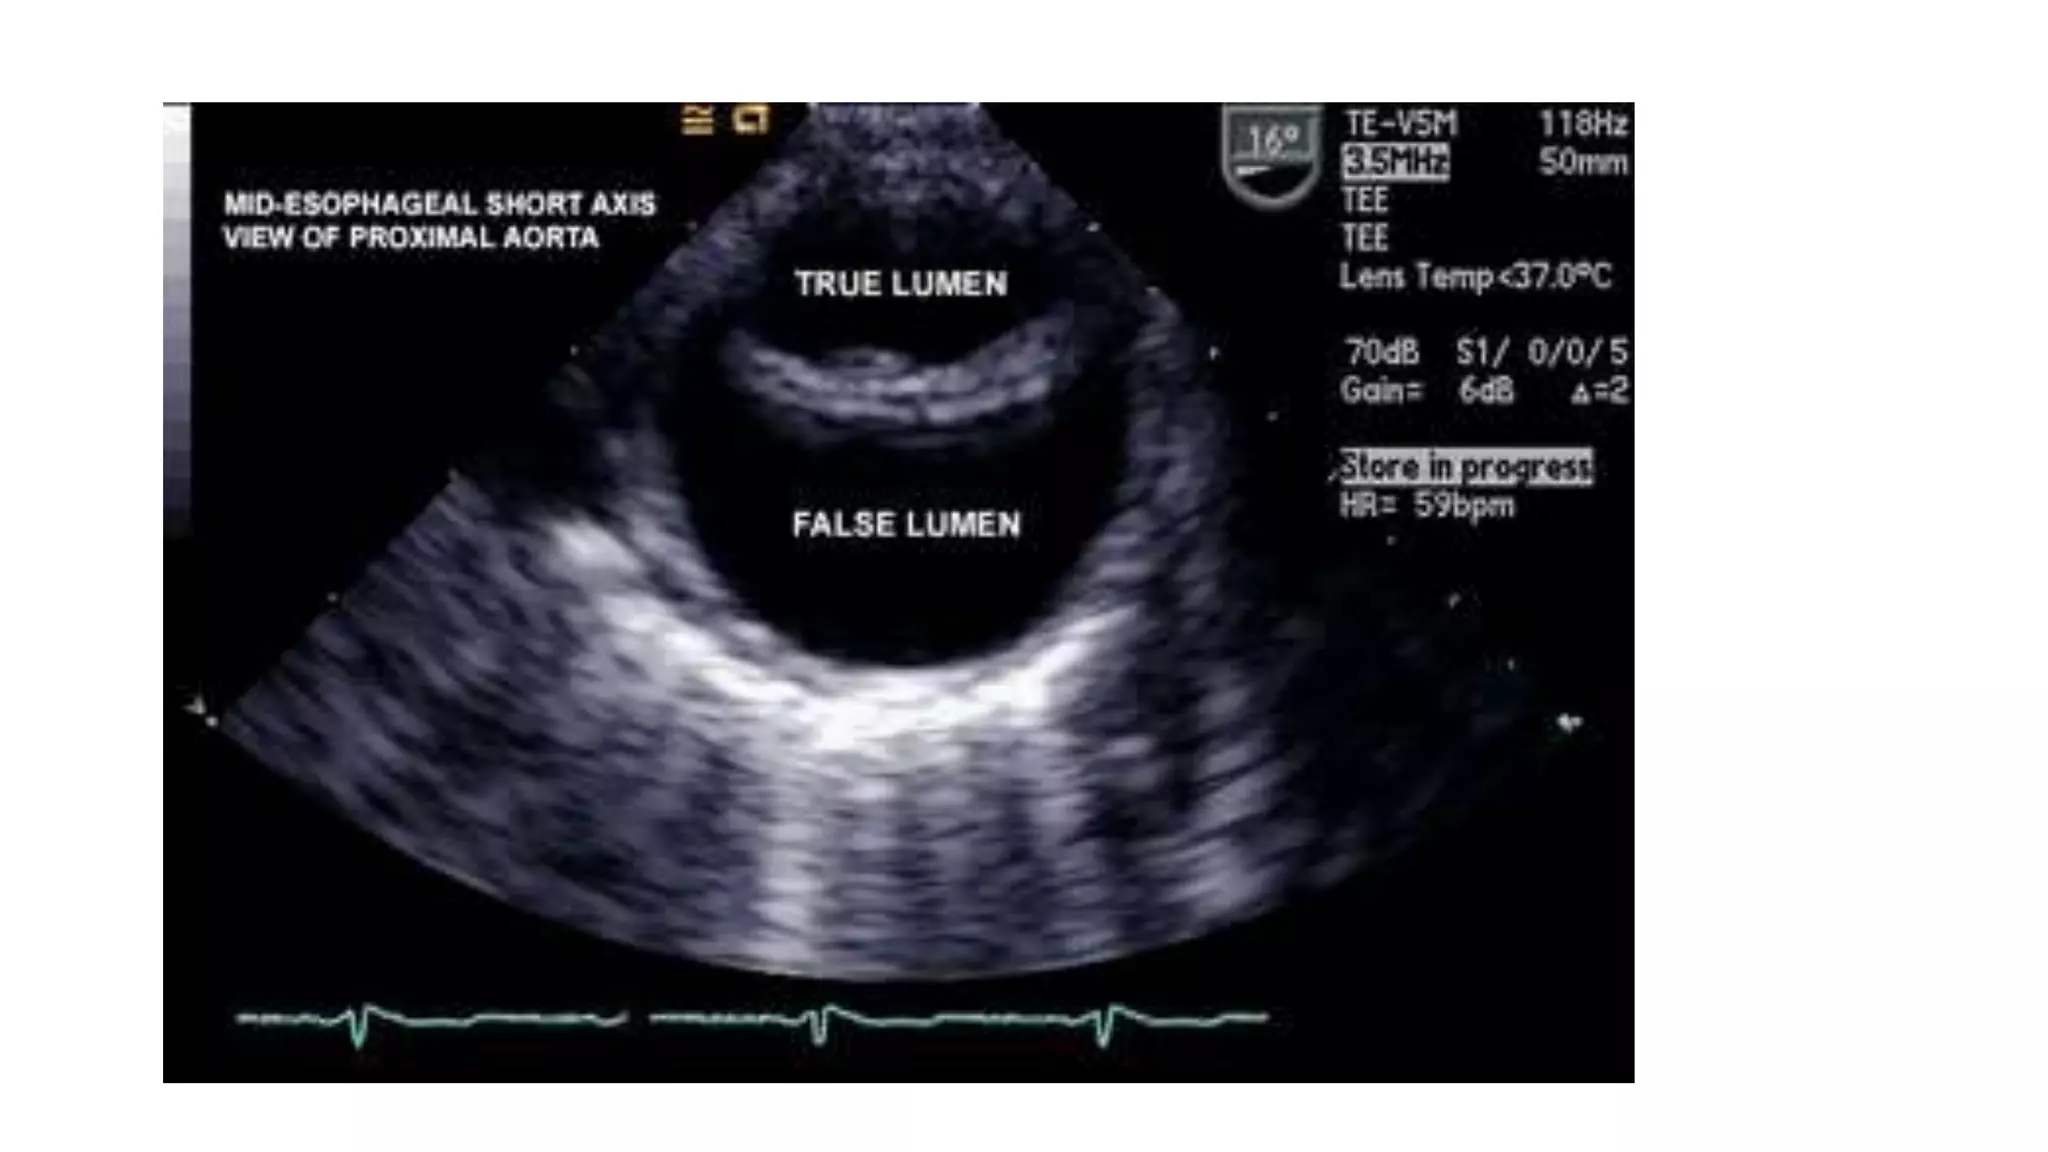

• Troianos et al described three cases of arterial dissection during CPB in

which TEE was found useful.

• Although provisional diagnoses were made on the basis of traditional

signs, TEE allowed assessment of the origin and extent of dissection.